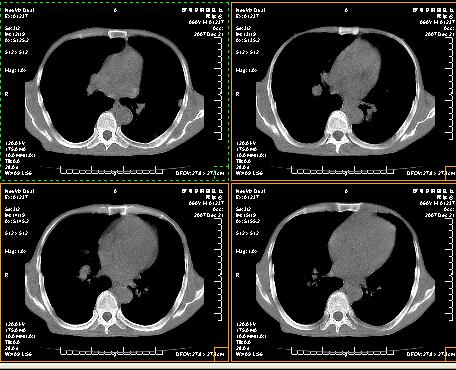

标题: CT12370:男.60岁.咳嗽发热胸痛. [打印本页]

标题: CT12370:男.60岁.咳嗽发热胸痛.

两肺示有散在大小不等类园形边缘不整密增高影.

考虑多发性转移瘤.请各位老师指导.

双侧胸壁见多发结节软组织密度灶,两肺内见广泛结节状、面团样影,两肺及胸膜多发性转移瘤。支持

根据:病变确实是多发,但大部分边缘不光滑,欠规整,密度不均匀。也就是说“大部分病灶不是典型转移瘤的表现”。转移瘤可以不典型,但如此大部分不典型,却是很少见的。结合发烧病史,考虑肺多发小脓肿或其他炎性病变,如霉菌等感染!建议痰培养,抗炎治疗后复查!